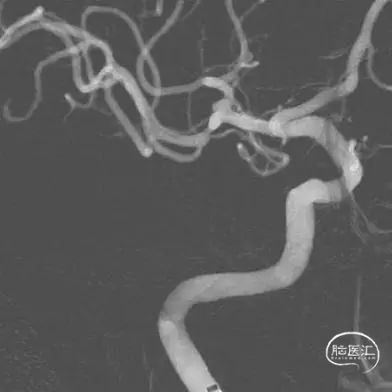

DSA结果:右侧大脑中动脉分叉部动脉瘤,大小约:2.2mmx1.7mm、瘤颈:约2.6mm,未破裂型。

术前影像